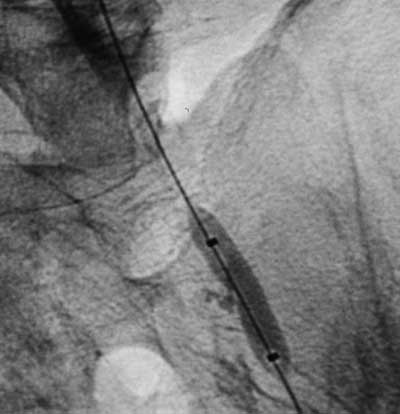

Имплантация артериального стента Белорусского производства.

Рис. 3. Предилатация стенозированного участка.